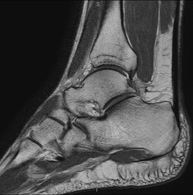

- Ankle MRI

Examination to study the joint and its frequent ligament injuries (sprains) as well as damage to other structures such as cartilage or bone. It is also very useful for diagnosing disorders of the Achilles tendon (tendinitis, ruptures). Duration: approximately 20 minutes. It is a radiation-free procedure.

- Ankle MRI arthrography

Examination to study injuries to small anatomical structures of the joint that are commonly injured in patients suffering from dislocation or chronic instability. Prior to the examination, a contrast fluid is injected into the joint, guided by X-ray imaging. The total duration of the two procedures is 50 minutes.